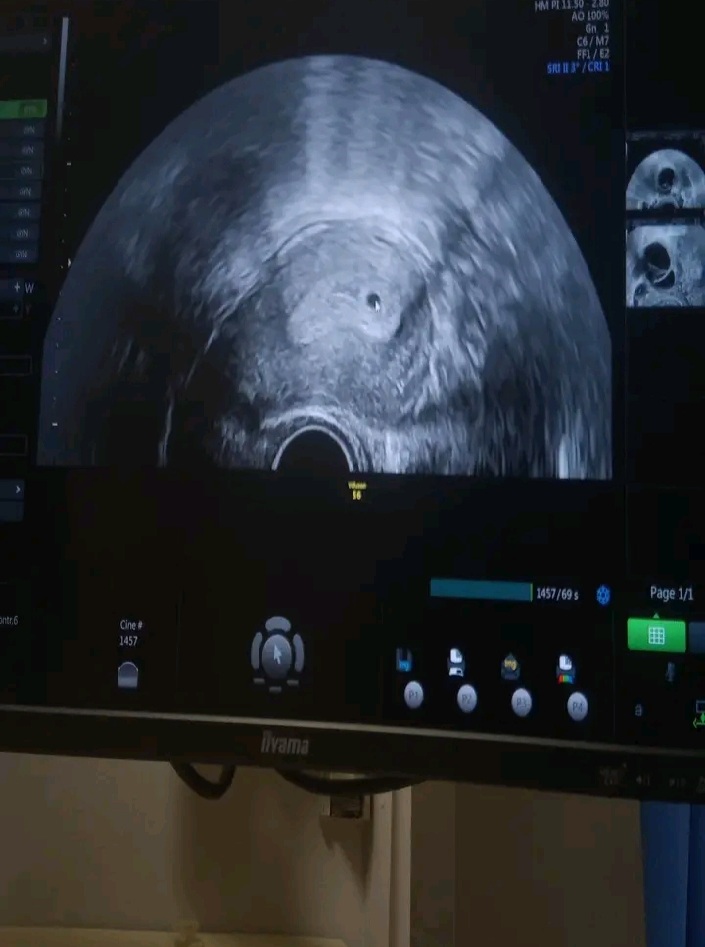

Ahoj všichni 🙈 chci vám něco oznámit co mě dost překvapilo.. dávala jsem tady těhu testy pozitivní...⚘ ale včera jsem byla v nemocnici protože se mi to už nezdálo bylo mi pořád blbě furt jsem zvracela bolení prsou motani hlavy dneska mám tepr 3 dny zpoždění ale včera jsem byla na ultrazvukové vyšetření a ukázalo tohle 🥰🥰 dva dny zpoždění včera taky ste to tak někdo měli?🖇

@martinka0209 ano to je váček pan doktor potvrdil těhotenství 🥰

@makovice88 ne já se nedivím já jsem spíše šťastná ale mě se už jednou stalo že jsem potratila a na ultrazvukové vyšetření nebylo nic proto to píšu takhle že mě moc překvapilo a jsem šťastná že v děloze už jde něco vidět 👌

Já jsem asi debil, ale nějak nechápu, co mám na tom ultrazvuku vidět, nebo kde přesně je problém 🙈.